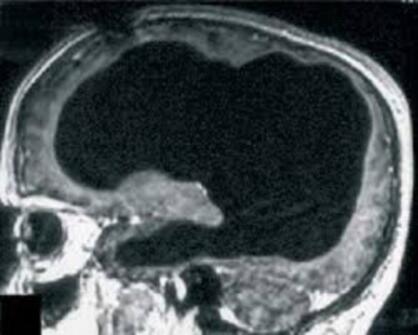

Các bác sĩ đã sửng sốt khi nhìn thấy 90% não bộ của một người đàn ông Pháp biến mất mà người này vẫn sống khỏe mạnh và sinh hoạt bình thường.

Mặc dù bị tổn thương tới 90% bộ não, một người đàn ông Pháp vẫn có thể sống và hoạt động bình thường, điều này đã thách thức sự hiểu biết của các nhà khoa học.

Sau khi tiến hành chụp X-quang não, các bác sĩ đã vô cùng kinh ngạc khi thấy phần lớn não bộ của người đàn ông này đã dần dần bị phá hủy trong suốt 30 năm qua bởi sự tích tụ của các chất lỏng trong não, tình trạng này được gọi là não úng thủy.

Mặc dù mô não chỉ còn lại một khoảng nhỏ, tinh thần và mọi hoạt động của người đàn ông này không bị ảnh hưởng. Chỉ số IQ của ông chỉ dừng ở con số 75 điểm, nhưng ông vẫn rất minh mẫn và luôn hoàn thành tốt công việc công chức của mình. Hiện tại ông đã kết hôn và có 2 con, sức khỏe của ông tương đối khỏe mạnh.